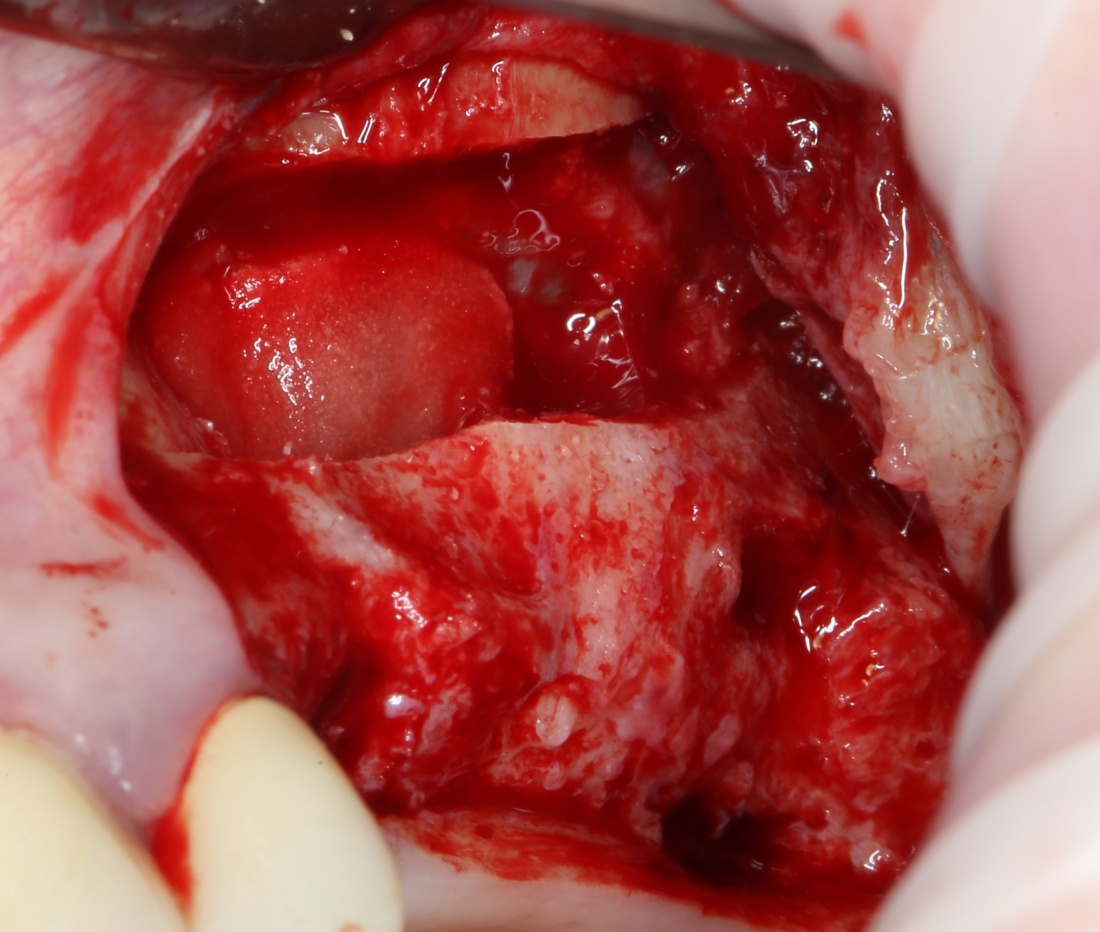

Ну хорошо. Швы сняли. Делаем разрез. Обрати внимание, что после всех проведенных операций у нас остается очень небольшой по ширине слой жевательной слизистой оболочки:

в связи с чем возникает резонный вопрос:

А нет ли здесь необходимости в дополнительной пластике десны?